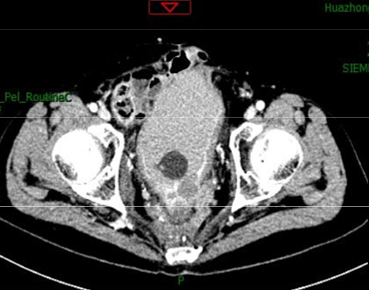

盆腔MRI:直肠癌局部复发侵犯前列腺,骶前,膀胱后壁及盆壁

腹部+盆腔MRI:盆腔及骶前脂肪间隙浑浊,散在渗出, 前列腺左侧,骶前左侧异常软组织影可疑累及膀胱左侧 后壁,右侧盆壁可见环形强化影,考虑转移

2019年5月及7月复查盆腔MRI:

(治疗4及8周期)

2020.4月肺部及盆腔CT: